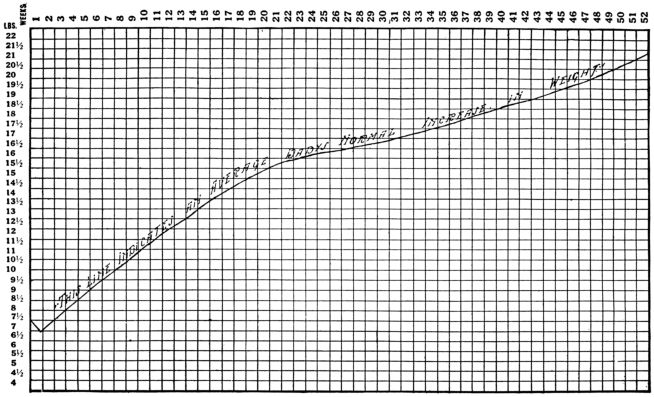

| 5. | Showing normal weekly gain in weight during first year of life | 454 |